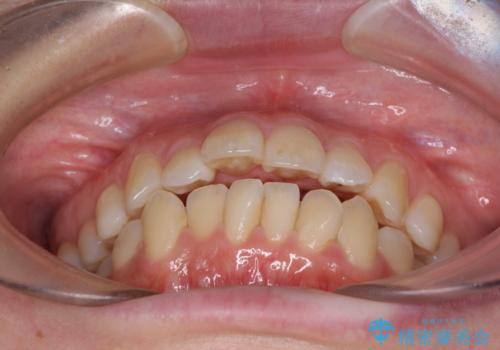

出っ歯を改善 目立たないワイヤー装置での抜歯矯正

- 口元の突出感と口の閉じにくさを気にして来院された患者様です。

上下左右第一小臼歯4本を抜歯し、ワイヤー装置にて口元を引っ込めるよう矯正治療を行うこととしました。

2年~2年半が治療期間の目安でしたが、順調に治療が進み、1年9か月で満足のいく歯列となりました。